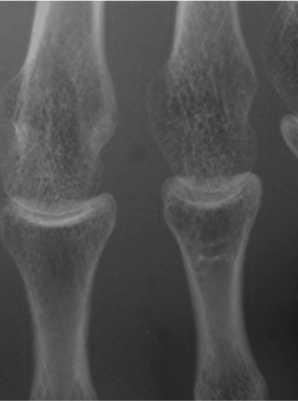

グリッド無し

ピクセル・アラインド・グリッド

一般的なグリッド

通常グリッド+グリッド目除去処理